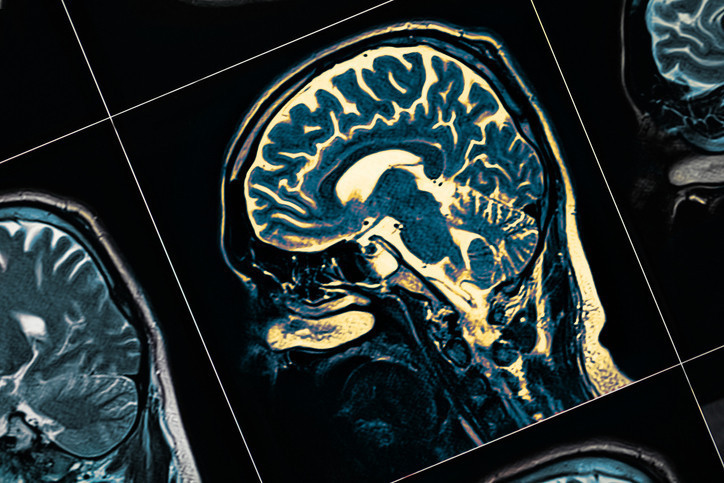

Orta yaşta yaşadığınız bazı depresyon belirtileri, 20 yıl sonra beyniniz için ciddi bir risk oluşturabilir mi? Yeni araştırma, demansı öngören altı kritik semptomu ortaya çıkardı. Peki hangi belirtilere dikkat etmek gerekiyor ve erken müdahale gerçekten fark yaratabilir mi?

Depresyon ve demans arasındaki bağlantı, uzun süredir araştırmacıların dikkatini çekiyor. Ancak yeni bir çalışma, orta yaşta görülen ve 20 yılı aşkın bir süre sonra bunamayı öngörebilen altı depresyon belirtisini ortaya koydu.

Demans vakalarının önümüzdeki yıllarda hızla artması bekleniyor. Uzmanlar, önlem alınmadığı takdirde 2060 yılına kadar yılda 1 milyon yeni demans vakasıyla karşı karşıya kalınabileceğini öngörüyor. Bu bağlamda yapılan araştırma hem bireysel farkındalık hem de sağlık politikaları açısından önemli sonuçlar sunuyor.